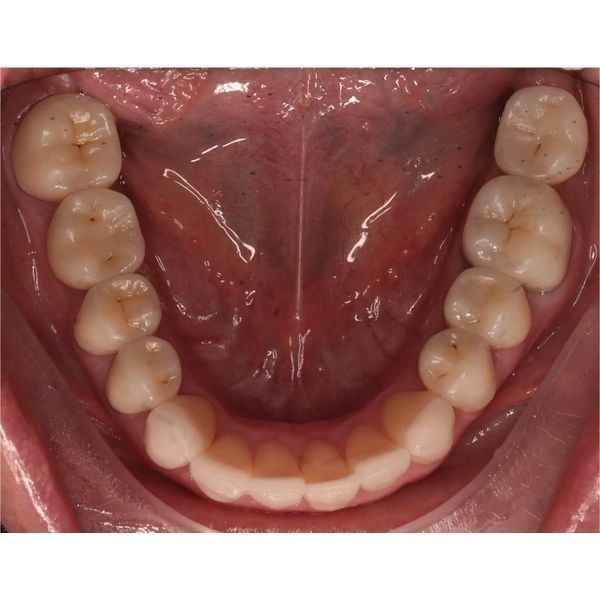

При осмотре выяснилось, что конструкции на центральных зубах хоть и выглядели эстетично, на них появились трещины и сколы, было нарушено краевое прилегание. Кроме того, у женщины наблюдалась стираемость зубов, особенно заметно стёрся нижний клык (зуб 3.3). На других зубах также присутствовали сколы.

Когда суставные головки приняли нормальное положение, наступил этап изготовления постоянных конструкций. Из непротезированных зубов у пациентки остались только нижние 4 резца и 2 клыка.

За весь период реабилитации пациентке:

- зафиксировали коронки и виниры на все зубы.